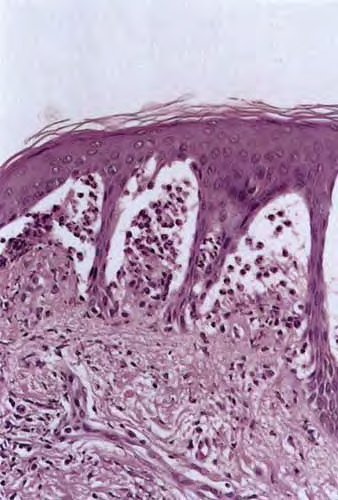

Histopathology

. The typical histologic features are best observed in erythematous skin adjacent to early blisters. In these zones, neutrophils accumulate at the tips of dermal papillae. With an increase in size to microabscesses, a significant admixture of eosinophils may be noted. As microabscesses form, a separation develops between the tips of the dermal papillae and the overlying epidermis; thus, the early blisters are multiloculated . The presence of fibrin in the papillae may give them a bluish appearance. Within 1 to 2 days, the rete ridges lose their attachment to the dermis, and the blisters then become unilocular  and clinically apparent. At this time, the characteristic papillary microabscesses may be observed at the blister periphery. For this reason, the inclusion of perivesicular skin in the biopsy specimen is of

utmost value. The papillary dermis beneath the papillae may have a relatively intense inflammatory infiltrate of neutrophils and some eosinophils. Many neutrophils may exhibit leukocytoclasis. Subjacent to this, a perivascular infiltrate composed of lymphocytes, neutrophils, and eosinophils may be apparent. the diagnostic finding of papillary microabscesses may not be present in all patients. Apoptotic keratinocytes may be noted above the papillary microabscesses.